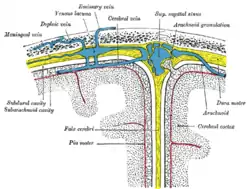

The dura mater has several functions and layers. The dura mater is a membrane that envelops the arachnoid mater. It surrounds and supports the dural sinuses (also called dural venous sinuses, cerebral sinuses, or cranial sinuses) and carries blood from the brain toward the heart.

The two layers of dura mater run together throughout most of the skull. Where they separate, the gap between them is called a dural venous sinus. These sinuses drain blood and cerebrospinal fluid (CSF) from the brain and empty into the internal jugular vein.

Arachnoid villi, which are outgrowths of the arachnoid mater (the middle meningeal layer), extend into the dural venous sinuses to drain CSF. These villi act as one-way valves. Meningeal veins, which course through the dura mater, and bridging veins, which drain the underlying neural tissue and puncture the dura mater, empty into these dural sinuses. A rupture of a bridging vein causes a subdural hematoma.

Dura mater (spinal section) Diagrammatic representation of a section across the top of the skull, showing the membranes of the brain, etc.

Diagrammatic representation of a section across the top of the skull, showing the membranes of the brain, etc. Diagrammatic transverse section of the medulla spinalis and its membranes